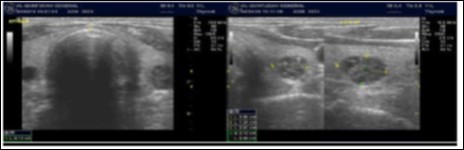

Parathyroid Glands Pathology:

In our study many patients were found to have nodules look very much like PT adenoma, Figure 7 below. At least, 4 patients were subsequently confirmed to have parathyroid adenomas, Figure 8 and 2 patients underwent surgery

Despite the fact that nodular pathology was found to be very prevalent among our study population, it has been found difficult to differentiate between thyroid and parathyroid pathology using ultrasound alone. However, some characteristics of the parathyroid glands might suggest parathyroid pathology in the context of the clinical picture of secondary or tertiary hyperparathyroidism which is very prevalent in ESKD patients’ populations.

Figure 7.Thyroid nodule suspicious for Parathyroid adenoma due to its location

Figure 8.Nodule that proven to be a parathyroid adenoma, volume =5265 mm3

There are 4 parathyroid glands (2 superior, 2 inferior) imbedded within the thyroid gland. The parathyroid glands are bean-like shape and small (20-40 mg) 25. Sonographically, the parathyroid glands have the following features 25:

Hyperplastic glands: hypoechoic, volume <500 mm3.

Nodular glands: hypoechoic. Volume >500 mm3

Histologically, if the excised gland has volume <500 mm3 it is said to be hyperplastic and if the volume is more than 500 mm3 it is nodular hyperplasia in 80% of cases26. In secondary HPT, the increase in the volume of parathyroid glands is associated with increase in vascularity, as evident in Color Doppler imaging 27.